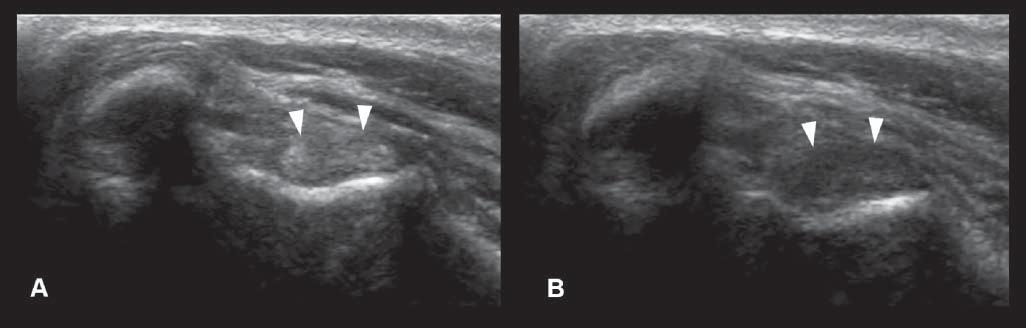

Anisotropy

Thisartifactismostcommonlydescribedinmusculoskeletalultrasoundandconsistsofadecreasein echogenicityofthestructure(suchasthetendonor ligament),duetoanobliqueposition(ratherthan perpendicular)oftheprobeonthebodypartbeing evaluated(Figure1.21).Thiscanbeeasilycorrectedby changingtheprobeangle.

Figure1.21. Anisotropy.A: Normalcross-sectionalappearanceofthebicepstendon(arrowheads),withtheprobebeing perpendiculartothestructure. B: Thedecreaseinechogenicityofthetendonisduetoanobliquepositionoftheprobe.This canbeeasilycorrectedbychangingtheprobeangle.Thisartifactcouldbemisinterpretedasacorelesion.